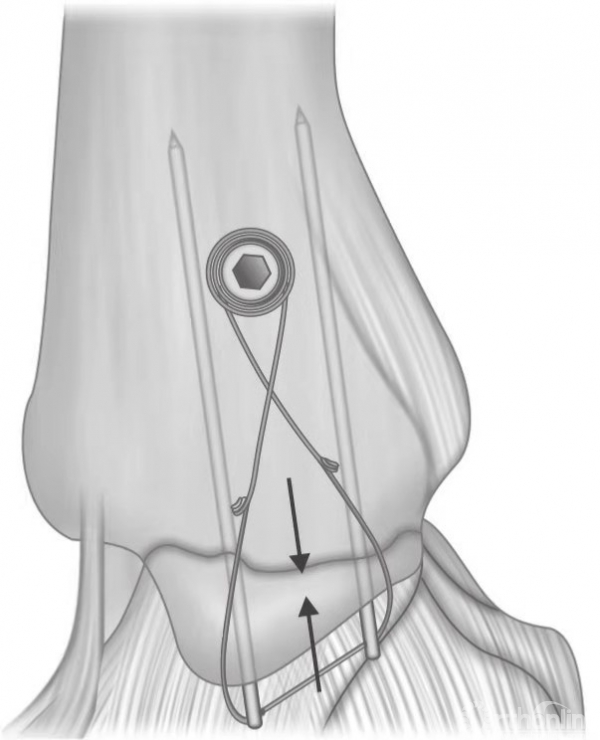

当发生内侧压缩时,可能还需要进行骨移植。如果内侧骨折片非常小,则固定时可用一枚螺钉和一枚克氏针或用两枚遵循静态张力带原理的克氏针(图20和图21)。

图20 旋后内收型踝关节骨折,内踝可用支撑钢板固定,外踝可用长克氏针固定。

图21 内侧骨折片非常小,则固定时可用一枚螺钉和一枚克氏针或用两枚遵循静态张力带原理的克氏针